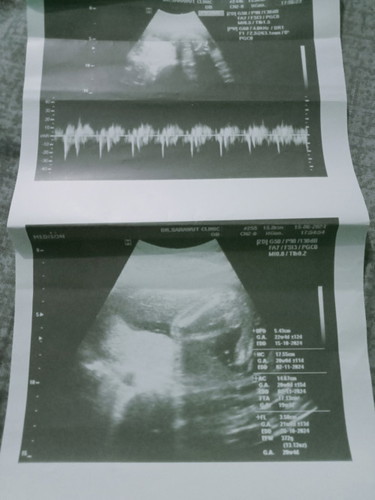

ภาพอัลตร้าซาวด์ตอน20วีค+ หมอบอกว่ายังไม่ชัด ตอนนี้29+2ยังไม่รู้เพศเลยค่ะ🤣🤣 25นี้ว่าจะไปซาวด์4มิติ